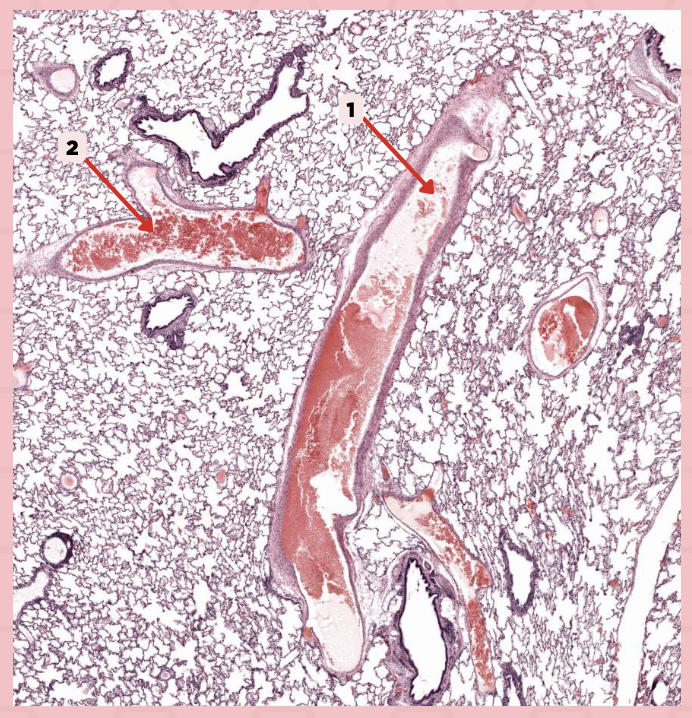

Bigger and smaller intrapulmonary bronchi

What are the two types of intrapulmonary bronchi?

Pseudostratified epithelium (bigger bronchioles), Simple columnar or cuboidal (smaller)

What are the types of epithelium in No. 3?

Interalveolar septa

Identify the structure labeled as 1.

Intrapulmonary bronchi

Identify the structure labeled as 2.

Bronchiole

Identify the structure labeled as 3.

Terminal bronchiole

Identify the structure labeled as 4.

Respiratory bronchiole

Identify the structure labeled as 5.

Alveolar ducts

Identify the structure labeled as 6.

Alveolar sacs

Identify the structure labeled as 7.

Deoxygenated blood

What type of blood does vessel No. 1 carry?

Connective tissue septae

Where would No. 2 be located?

Pulmonary artery

Identify the structure labeled as 1.

Tributary of pulmonary vein

Identify the structure labeled as 2.

Oxygenated blood

What type of blood does this vessel supply?

Bronchial artery

Identify the structure labeled as 1.